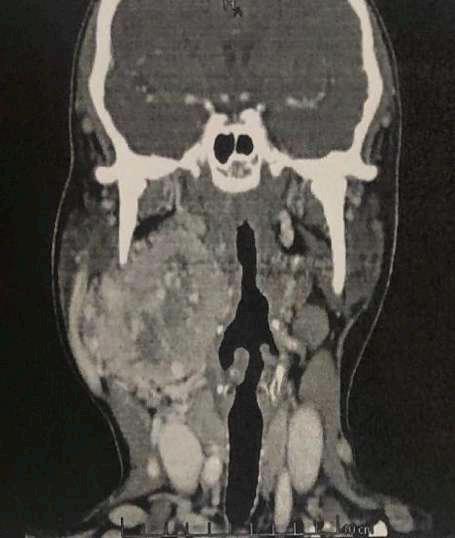

2.C. TUMOR DE CUERPO CAROTÍDEO + OCLUSIÓN DE RAMA ARTERIAL

TAC (imagen B): Tumor de cuerpo carotídeo derecho, shamblin III

A B

RETINAL CON ISQUEMIA MACULAR OD

Caso aportado por Dr. Cristian Sánchez

Clínica:

AV: OD CAE =0,2 / OI 0,8

PIO: OD 10/ OI: 16

BMC: Polo anterior normal

FO: Oclusión de la arteria ciliorretinal con isquemia macular OD

Obstrucción de la arteria ciliorretinal (OACR)

ü La arteria ciliorretiniana esta presente en 15-30% de los ojos

ü Es rama de arterias ciliares cortas posteriores

ü La etiología de la OACR suele estar relacionada con enfermedad carotídea u otros procesos tromboembólicos relacionados con estados de hipercoagulabilidad y autoinmunidad.

ü El diagnóstico suele ser fundoscópico con la visualización en nuestro caso del área retineana isquémica en el terrirotio de la arteria ciliorretineana y la visualización del embolo.

Vila-Arteaga, J., Suriano, M. M., & Martínez-Lajara, A. (2017). Obstrucción de la arteria ciliorretiniana durante el embarazo. Archivos de La Sociedad Española de Oftalmología, 92(9), 406–411. doi:10.1016/j.oftal.2016.10.020

ü

En las obstrucciones arteriales retineanas en la angiografía con fluoresceína en fase aguda existe un retraso marcado en el relleno de la arteria central de la retina o de sus ramas, con hipofluorescencia a lo largo de todo el angiograma de los territorios isquémicos por falta de relleno y efecto pantalla por el edema neurorretiniano (Imagen E y F). ü Campo visual computarizado 30-2: Mide los 30º temporales y nasales. En este caso el defecto en el campo visual es concordante con la clínica de la paciente (Imagen G y H).

E F

H

G